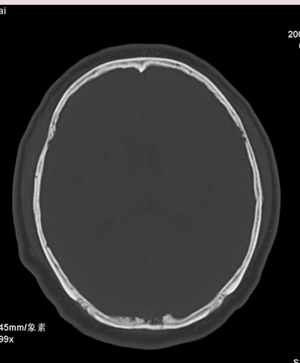

肢体活动肌力均正常。临床印象:脑血管病变。ct意见:脑软化灶,腔梗,请看看枕部病变是脑膜瘤,血管畸形还是其它

1.右基底节区脑软化灶。

2.右顶后部病变,脑膜瘤可能性大。

建议:强化扫描。

右侧基底节腔梗。

右顶后部血管畸形。